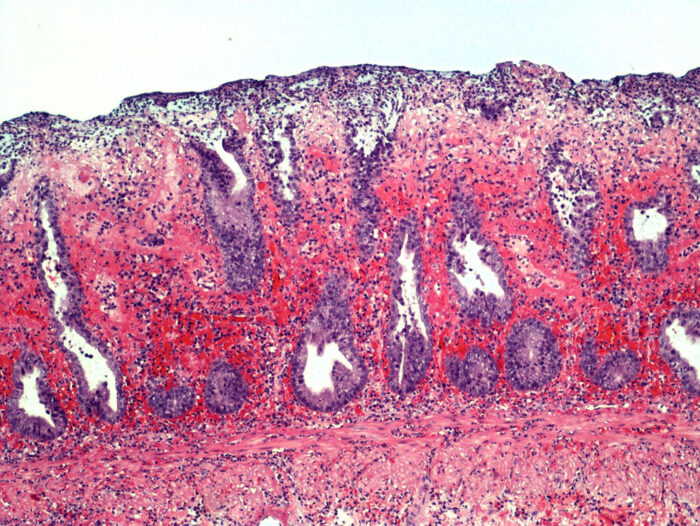

Laboklin: Akute hämorrhagische Proktitis bei einem Hund (Hämatoxylin-Eosin-Färbung, 100x). Bildquelle:Dr. Ulrike Schwittlick, Laboklin GmbH & Co. KG

Intestinales Mikrobiom beim Hund

LABOKLIN aktuell 2019Von Laboklin | Bad Kissingen17. Juni 2019

Viele Bereiche des Körpers sind bei Hunden mit den unterschiedlichsten Bakterien besiedelt…